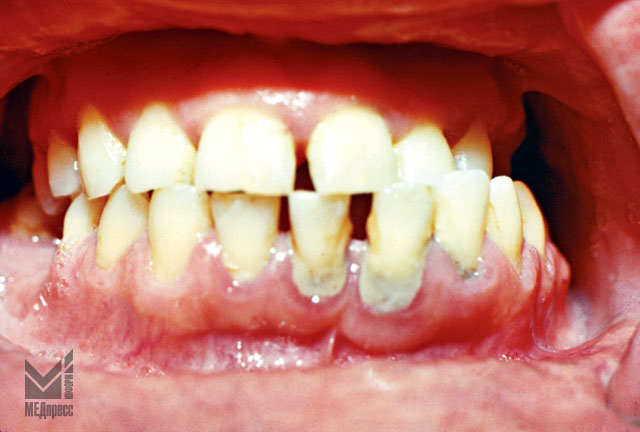

Рис. 7.Открытый прикус. Деформация челюстей и десневого края. Застойная гиперемия, отек. Оголение шеек центральных резцов, зубной камень.